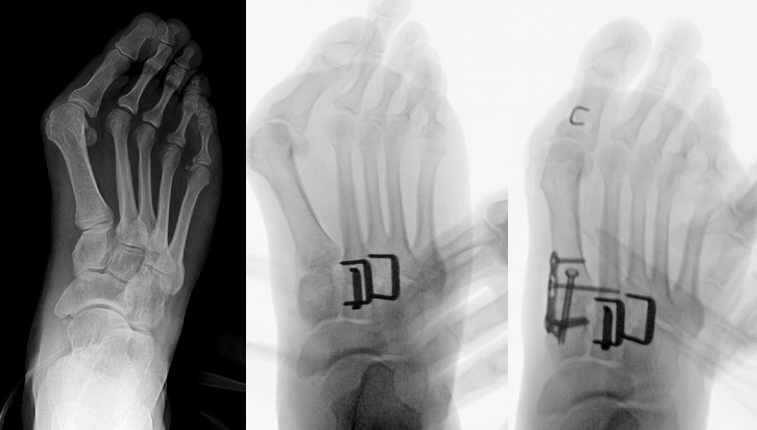

Surgical management in this situation requires a mindset shift: we must address the metatarsus adductus before proceeding with the hallux valgus reconstruction. By performing osteotomies of the second and third metatarsal bases, or my preference, arthrodesis of the second and third tarsometatarsal articulations (see photos), we effectively move the lesser metatarsals laterally. This creates the necessary real estate to correct the first ray. While this approach significantly increases operating room time and extends the patient's postoperative convalescence, failing to recognize and treat the MA essentially guarantees a compromised outcome and high recurrence rate.